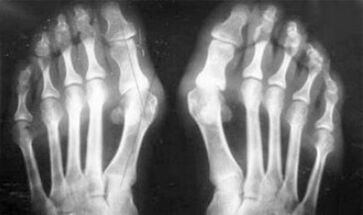

The difference between arthritis and arthrosis of the fingers and hands of the hands is that the first disease is cured and the second is not.With arthritis, the synovial shell and the capsule of the joint is touched.

The defeat of the cartilage and bone tissue occurs only in the late stages in a neglected state.With arthrosis, the cartilage tissue is first affected, and then bone, inflammation of the synovial membrane is of secondary origin, that is, it develops against their background.